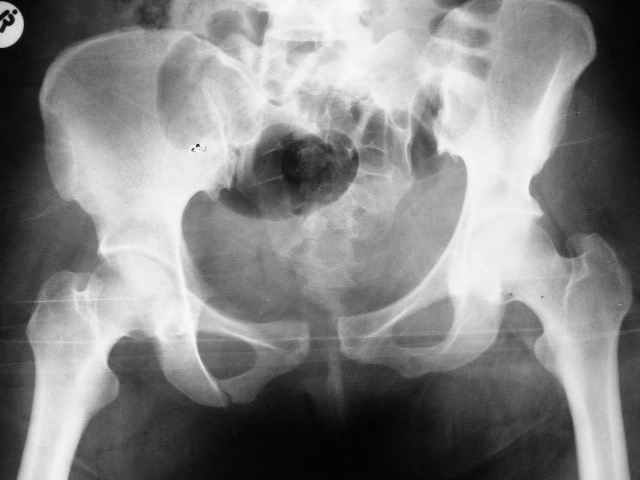

Больная 28 лет от роду попала в ДТП 12.12.04Что бы вы предложили.заранее признателен,Евгений И Чекашкин

Сегодня утром прооперировал: на симфиз пластину на 4 винтах и два 6.5 мм винта с неполной резьбой на левое крестцово подвздошное сочленение. (пришлось открыть - девушка весьма внушительной комплекции и пропальпировать крыло и ости не представлялось возможным, спасительного в таких случаях набора канюлированных винтов в госпитале нет). Проконтролировал качество репозиции ЭОПом - остался доволен.

К всеобщему глубокому сожалению и огорчению, больная погибла через 40 мин после возвращения из операционной в палату,по всей видимости, от тромбоэмболии. (внезапное нарушение сознания, кардиореспираторный дистресс)

хотя с первого дня поступления , опасаясь ТЭЛА (женщина, полная, постельный режим, травма таза первые три недели...) я назначил ей гепарин. Реанимировали в течении 30-40 мин (интубировали, дефибриллировали непрямой массаж сердца и тд... но безуспешно...

Сегодня сходил на аутопсию : большой тромб на бифуркации лёгочной артерии.....